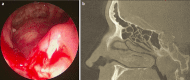

Endonasal endoscopic sinus surgery is the standard procedure for surgery of most paranasal sinus diseases. Appropriate frame conditions provided, the respective procedures are safe and successful. These prerequisites encompass appropriate technical equipment, anatomical oriented surgical technique, proper patient selection, and individually adapted extent of surgery. The range of endonasal sinus operations has dramatically increased during the last 20 years and reaches from partial uncinectomy to pansinus surgery with extended surgery of the frontal (Draf type III), maxillary (grade 3-4, medial maxillectomy, prelacrimal approach) and sphenoid sinus. In addition there are operations outside and beyond the paranasal sinuses. The development of surgical technique is still constantly evolving. This article gives a comprehensive review on the most recent state of the art in endoscopic sinus surgery according to the literature with the following aspects: principles and fundamentals, surgical techniques, indications, outcome, postoperative care, nasal packing and stents, technical equipment.